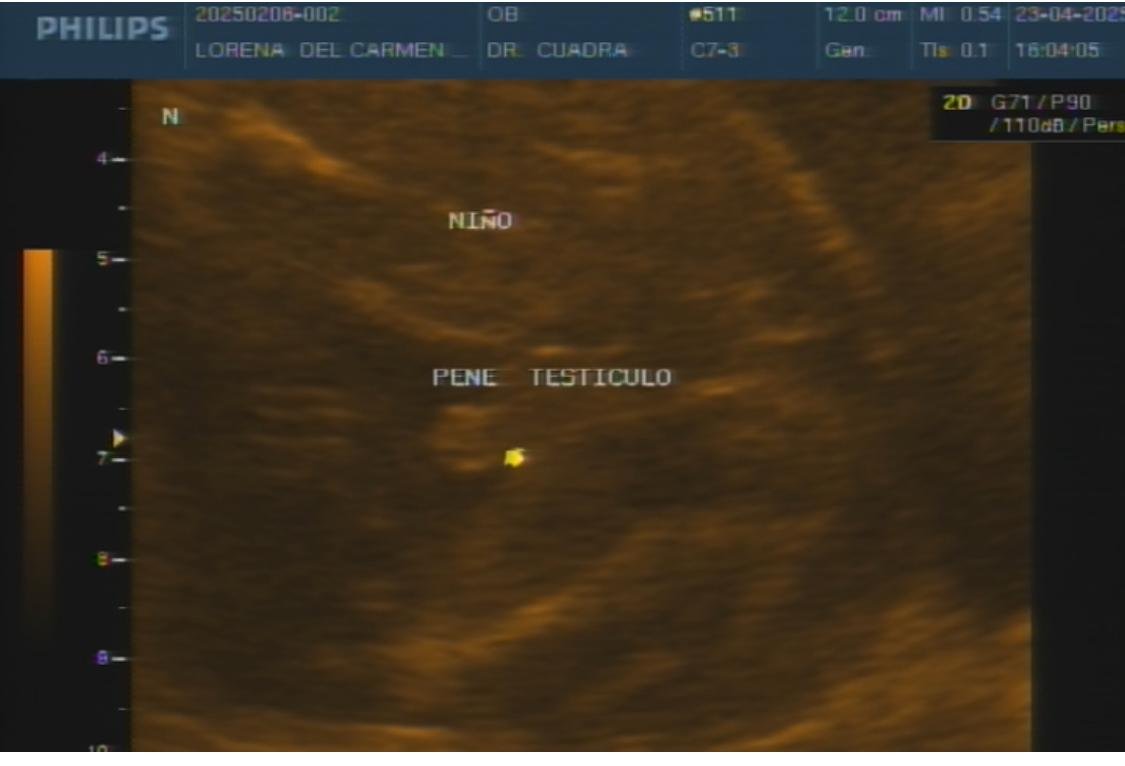

- Ultrasonografía para determinar el sexo fetal (a partir del segundo trimestre).

Galería de ultrasonografía de embarazo

Videos de ultrasonografía de embarazo